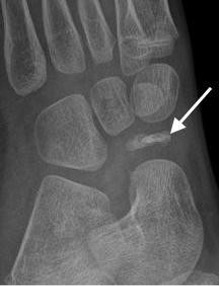

Kohler’s disease with flattening and sclerosis of the navicular (arrow)